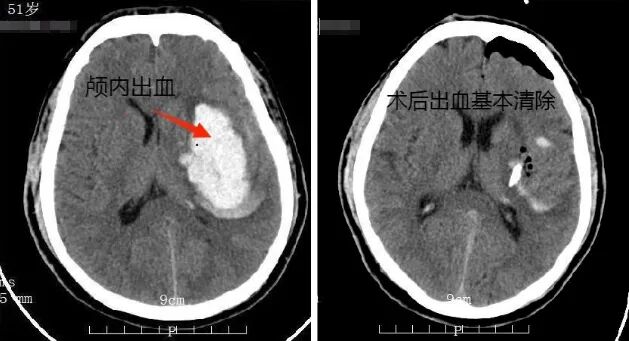

案例分享:4cm切口创造生命奇迹

51岁的张先生突发脑出血并逐渐昏迷,CT显示脑内血肿达50ml,命悬一线!经神经外科团队评估后最终选择“神经内镜微创手术”,仅切开4cm小口,用“神经内镜”精准清除血肿,术后第二天张先生就逐渐清醒!

荆门市人民医院神经外科通过神经内镜,利用骨孔或直径2~3cm的骨窗治疗颅内病变,具有创伤小、视野清晰、范围广、手术疗效佳、并发症少等特点。近年来,其在颅脑出血性疾病中的应用优势愈发明显,脑出血可以进行微创手术清除血肿,再也不用让患者“脑洞大开”了。